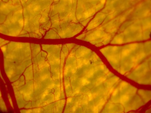

1. 激光治疗血管和色素性疾病中的热物理问题

• 血管性皮肤病(由畸形毛细血管扩张引起,治疗原理为血红蛋白吸收激光能量导致病变血管死亡)

血管热损伤机理

血液对1064nm Nd:YAG激光的吸收强化